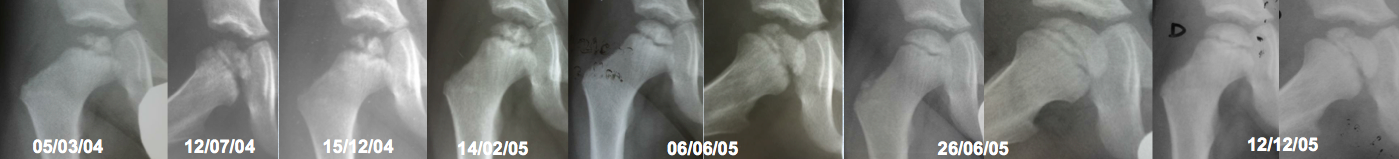

Enfermedad de Legg-Perthes-Calvé recurrente. Descripción de un caso y revisión de la literatura. [Recurrent Legg-Perthes-Calvé disease. A case report and literature review]